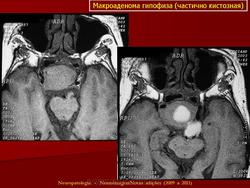

Кистозная аденома.

Приложения:

21.kistoznaya_adenoma_gipofiza.jpg22.kistoznaya_adenoma_gipofiza.jpg